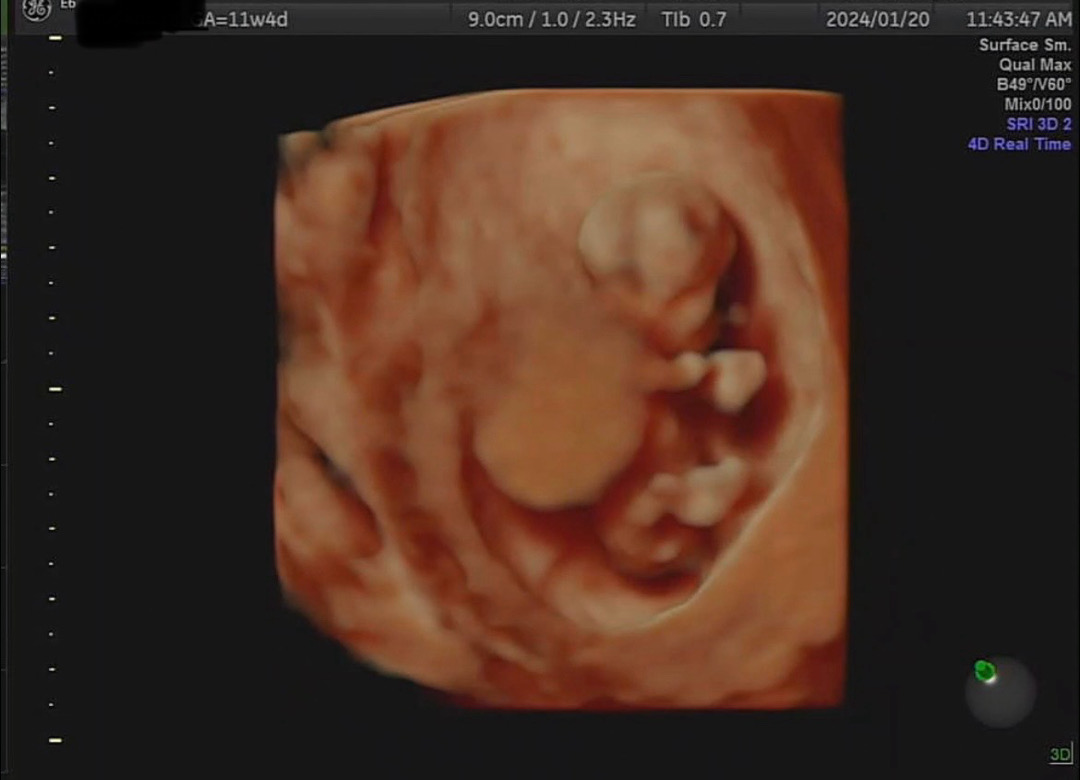

11주 4일 정밀검사 1차 했어요

정밀검사로 보는 아가는 너무 신기해요 초음파상으로 . 만 하던 게 이제 커서 5센티가 넘는다고 하니 너무 신기하네요 .. 🥹 최근에 감정기복도 심하고 스트레스도 받아서 걱정했는데 역시 ..아가는 생각보다 강하게 크고 있더라구요 … 🫶🏻 한달 뒤 성별 알 수 있다고 하는데 한달이 너무 길어요 🥺🥺 모두들 정밀 초음파 보고 오셨으면 같이 얘기 나누어요 😍😍